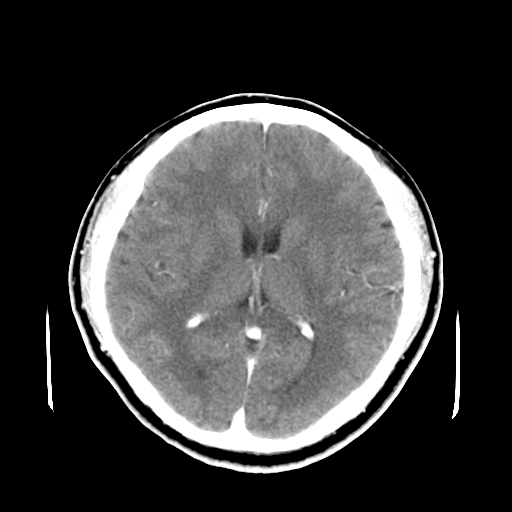

标题: CT16447B:(续)增强扫描图像。

患者今日做ct增强检查,现补传增强扫描图像。

松果体钙癍增大,无其他改变,定不了性

一般认为大于1cm为异常。